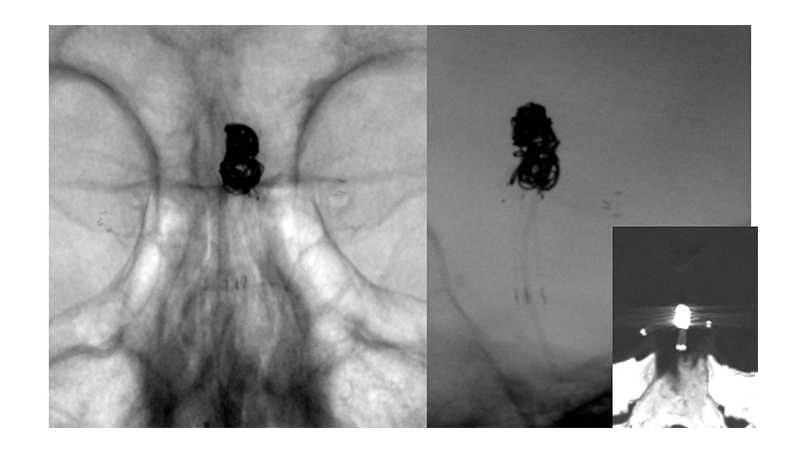

Εικόνα 4: Έχουν τοποθετηθεί τα δύο stents και έχει γίνει η πλήρωση του ανευρύσματος με coils.

Εικόνα 5, 6: Πλήρης απόφραξη του ανευρύσματος με Y-stenting και coils, αμέσως μετά τον εμβολισμό.